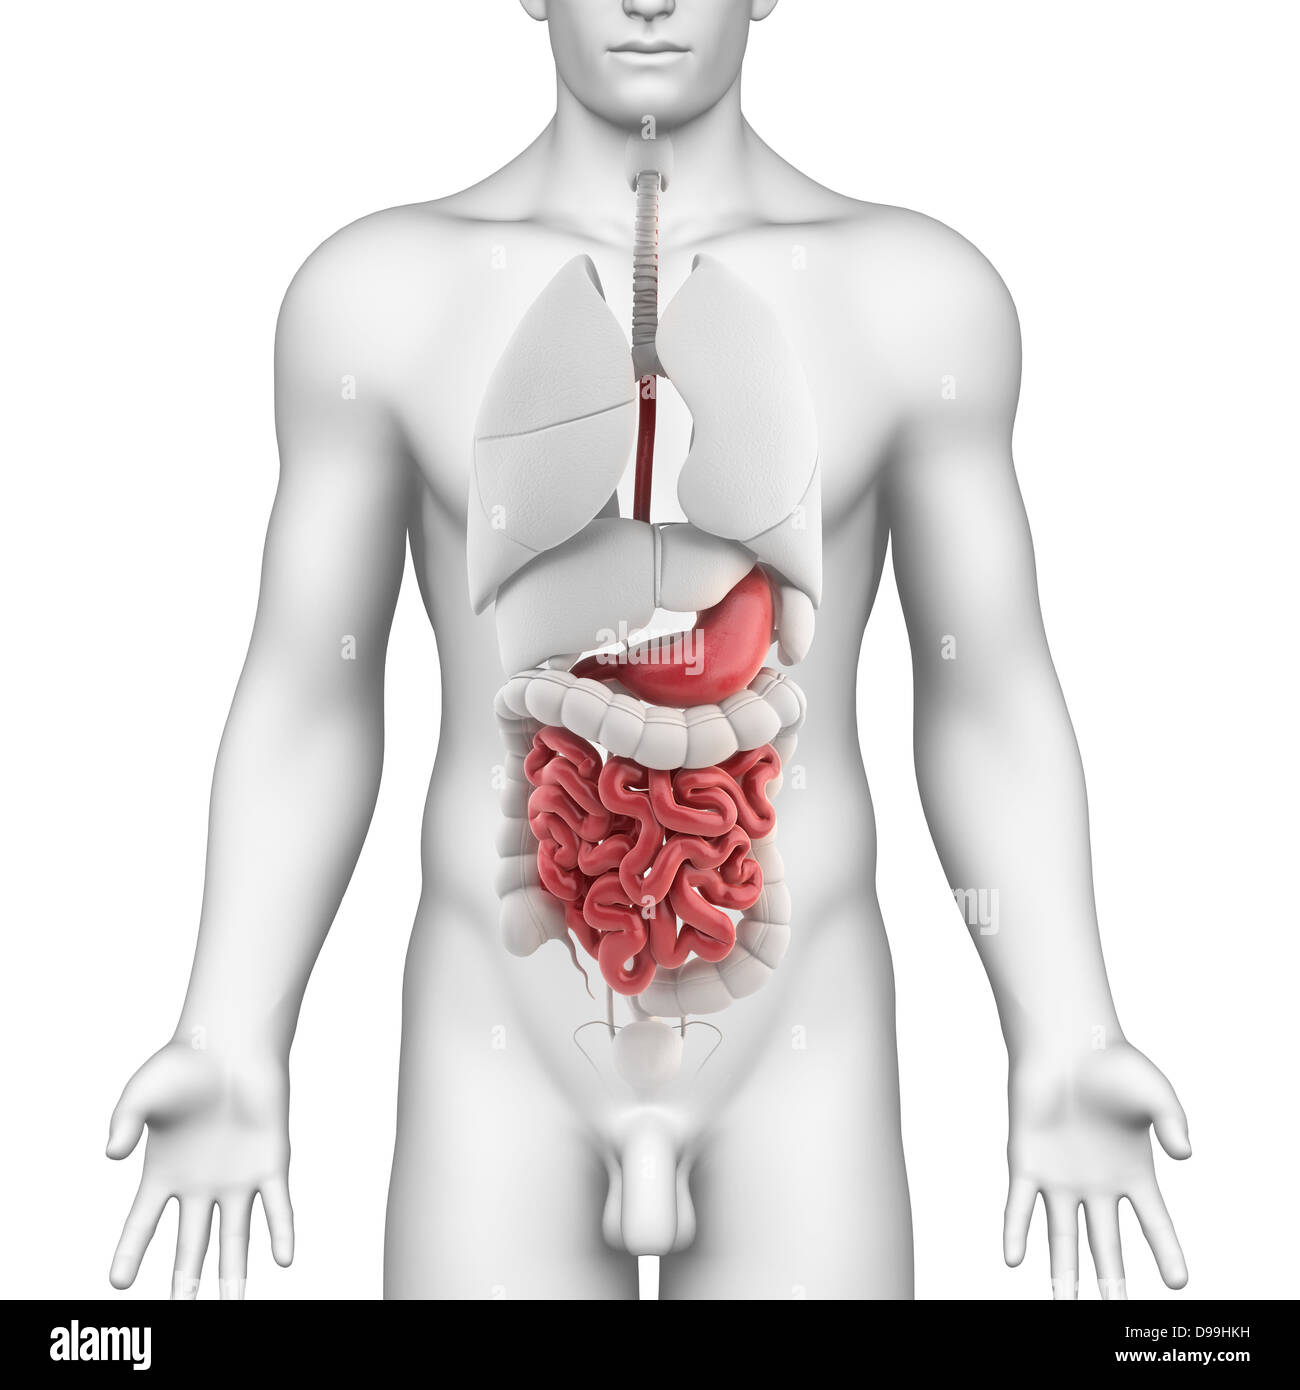

Männchen anatomie Stockfotos & Bilder

RFPAYTH0–Innere Organe, männlichen Körper - schematische Darstellung der menschlichen Anatomie Illustration - auf weißem Hintergrund.

RF2GB8D4J–3D-Darstellung des Verdauungssystems der männlichen Anatomie, zusammen mit anderen inneren Organen. Glasbild auf blauem Hintergrund, Vorderansicht.

Suchergebnisse für Männchen anatomie Stock-Fotos & Bilder (86,080)